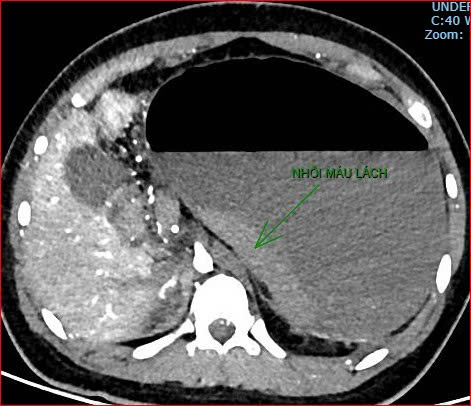

Khoảng 21 giờ 40, kết quả chụp CT cho thấy bệnh nhân rơi vào tình trạng cực kỳ nặng và hiếm gặp, bao gồm: xoắn dạ dày, nhồi máu thận trái, nhồi máu lách, viêm đầu tụy, viêm hỗng tràng, kèm dịch ổ bụng và tràn dịch màng phổi, trên nền bệnh nhân mắc hội chứng Down và tim bẩm sinh.

Hình ảnh chụp CT ổ bụng cho thấy dạ dày giãn lớn, xoắn bất thường; kèm tổn thương nhồi máu lách và viêm tụy trên nền ca bệnh hiếm, diễn biến đặc biệt nặng – Ảnh Bệnh viện cung cấp